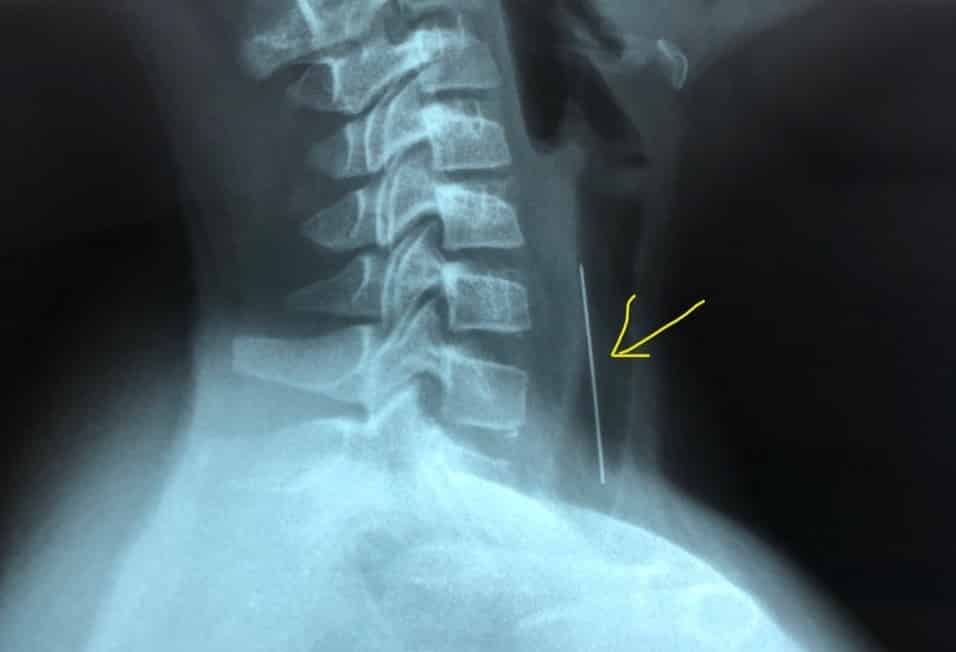

Tại bệnh viện địa phương, bệnh nhi được bác sĩ khám, chụp XQuang, nghi ngờ có dị vật ở khí quản nên được chuyển đến Bệnh viện Nhi Đồng 1 (TP.HCM) với chẩn đoán: Theo dõi dị vật đường thở.

Theo nhận định ban đầu của phẫu thuật viên khi nội soi, dị vật là 1 cây kim có 1 đầu nhựa quay xuống dưới, đầu nhọn quay lên trên và đâm vào thành khí quản khoảng 1cm chiều dài. Bác sĩ nhận định có thể khi rớt vào đường thở, đầu nhọn của kim luôn nằm phía trên, sau đó là phản xạ ho của bé làm cho kim đâm vào niêm mạc của khí quản. Kim nằm ở khí quản cách cựa khí quản khoảng 4-5cm.

Một cây kim dài hơn 4 cm với 1 đầu nhựa màu cam đã được gắp ra khỏi khí quản của bệnh nhi. Sau soi gắp dị vật, đường thở bé ổn, không chảy máu. Hiện tình trạng sức khỏe của bé bình thường, không còn đau, khó thở và ăn uống được.